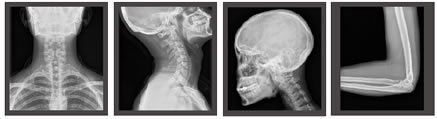

Le DigiEye 280 est un système de radiographie conventionnelle, reposant sur le sol et équipé de la technologie innovante de Mindray.

Des technologies de pointe pour une qualité d'image remarquable

Applications